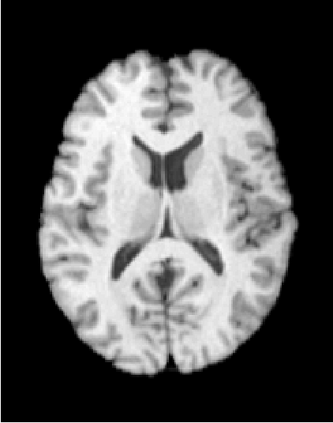

The purpose of this work is to contribute to the state of the art of deep-learning methods for diffeomorphic registration. We propose an adversarial learning LDDMM method for pairs of 3D mono-modal images based on Generative Adversarial Networks. The method is inspired by the recent literature for deformable image registration with adversarial learning. We combine the best performing generative, discriminative, and adversarial ingredients from the state of the art within the LDDMM paradigm. We have successfully implemented two models with the stationary and the EPDiff-constrained non-stationary parameterizations of diffeomorphisms. Our unsupervised and data-hungry approach has shown a competitive performance with respect to a benchmark supervised and rich-data approach. In addition, our method has shown similar results to model-based methods with a computational time under one second.